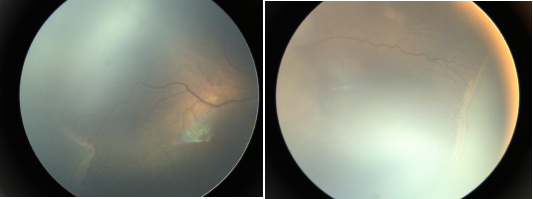

正常眼底

早產(chǎn)兒視網(wǎng)膜病變

先天性白內(nèi)障

以上圖片均來源于網(wǎng)絡(luò)

常見致盲性眼病如早產(chǎn)兒視網(wǎng)膜病變、先天性白內(nèi)障、視網(wǎng)膜母細(xì)胞瘤、先天性青光眼等。如能早發(fā)現(xiàn)并及時(shí)有效干預(yù)治療,能最大限度保護(hù)寶寶的視覺正常發(fā)育,避免致盲。尤其是早產(chǎn)兒、低出生體重兒,以及具有眼病高危因素的新生兒更容易發(fā)生致盲性眼病,需要及時(shí)進(jìn)行新生兒致盲性眼病篩查。